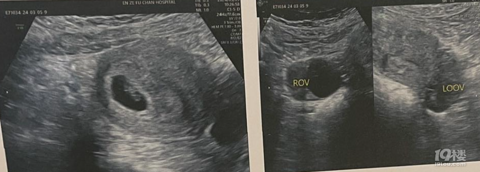

产期:2023.07.29(大概吧,推算出来也不一定准)建卡医院:(还未建卡)产检医院:黄岩妇幼胎宝宝小名:不知啊生产医院:未定说起来,我的大姨妈一直不准确,因此就抱着随缘的心态,叶酸啥啥都没吃。在姨妈整整一个月没来的时候我感冒了(可能是怀孕引起的现象),又吃了感冒药。过了半个月姨妈还不来,我才觉得是不是要测一测。果然,两条杠,还很明显,就去了医院。